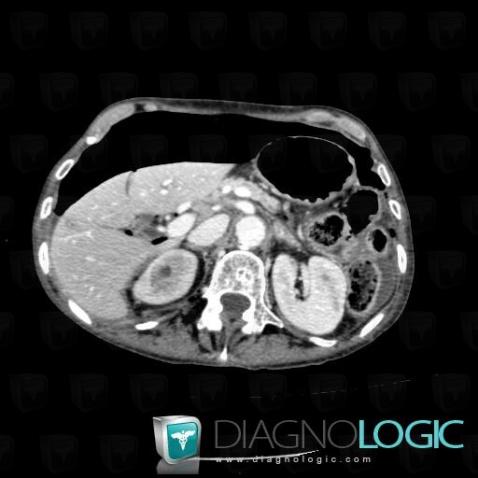

Pneumoperitoneum, Mesentery / Peritoneum, CT

Here is the specific information in the key image above:

- Diagnosis Pneumoperitoneum, Location(s) Mesentery / Peritoneum, with gamuts